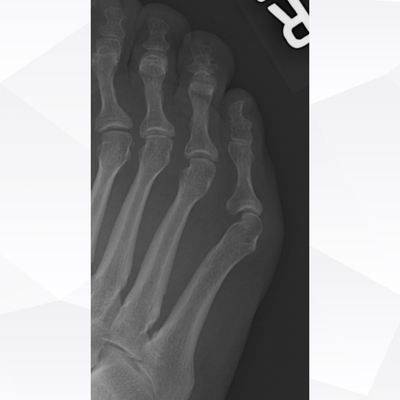

Click on an image below to view more info.